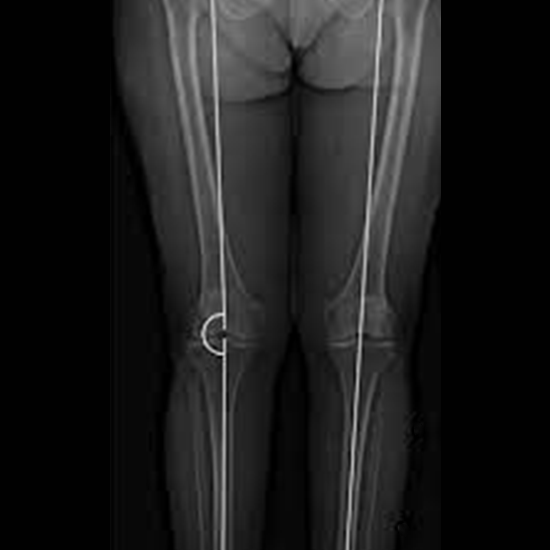

X-Ray Scanogram Both Lower Limbs

X-ray equipment transmits a beam of radiation through the legs during a Scannogram; both Lower Limbs X-ray and an image are recorded on a particular film or a computer. The image depicts the soft tissues and bones, including the femur, tibia, and fibula, allowing physicians to measure and compare the length of the legs.